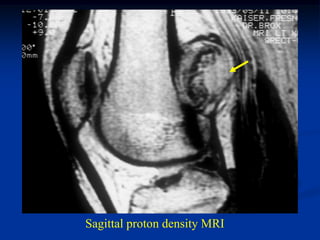

CLASSIC

Case #122

25 year male

osteochondroma

tibia

Lateral view

cartilage cap

fatty marrow

Sagittal T-1 MRI

Macro section